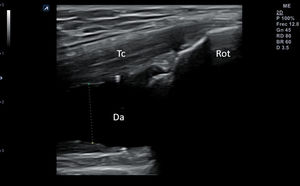

Punciones ecoguiadas en medicina familiar52–59Técnica de exploraciónPara realizar punciones superficiales, es preferible el uso de la sonda lineal de alta frecuencia por su mejor resolución superficial. Así, los accesos vasculares, los bloqueos neurales o las infiltraciones articulares, se beneficiarán de una guía visual de alta definición que permita una buena imagen de las estructuras menos profundas. En los drenajes de gran cantidad de fluido, o lesiones en profundidad, está indicado el uso de la sonda convexa de baja frecuencia. La toracocentesis o la paracentesis (en nuestro caso generalmente diagnósticas y rara vez terapéuticas) se beneficiarán del uso de esta sonda.

La punción se puede hacer en el eje largo de la sonda, denominada también «en plano» (fig. 14), con la aguja entre 30 y 45° de inclinación respecto a la superficie, lo que permite visualizarla en todo su trayecto, y lo hace muy recomendable cuando haya riesgo de lesionar estructuras cercanas. La aguja aparecerá en la pantalla como una línea hiperecogénica brillante con artefacto de reverberación (al ser un objeto metálico, se dibujarán líneas paralelas hiperecogénicas por debajo de la misma por un efecto espejo). Para poder visualizar correctamente todo el trayecto de la aguja, esta debe orientarse en el mismo plano de corte de la sonda.

En otros casos interesará realizar un abordaje en el eje corto de la sonda, denominado «fuera de plano»(fig. 15) introduciendo la aguja perpendicular a la sonda, en su parte media, de modo que en la pantalla será visible únicamente la punta. Esta técnica no permite seguir el trayecto completo de la aguja en un solo corte, pero ofrece una imagen precisa de su punta. El uso de una u otra técnica dependerá de las preferencias del profesional que realice la técnica, del tipo de punción y de las condiciones anatómicas de la zona.